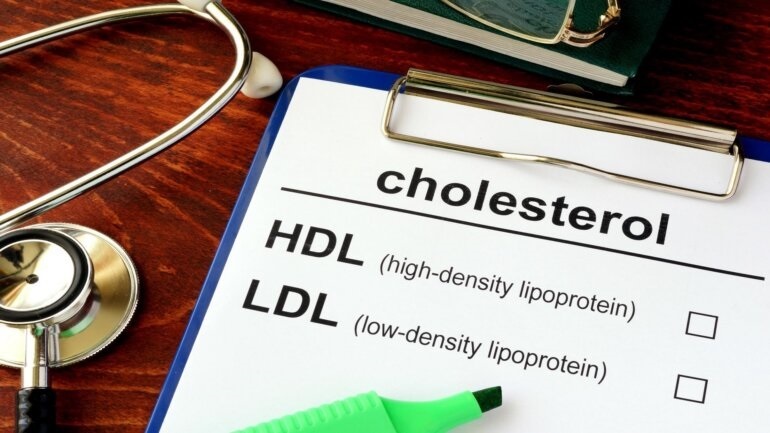

Μελέτη βρήκε ότι λήψη υψηλών δόσεων βιταμίνης D δεν επηρέασε τη συχνότητα εμφάνισης καρδιαγγειακών παθήσεων ή καρκίνου